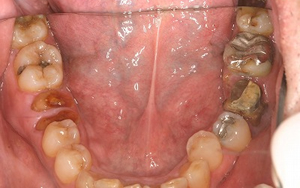

患者さまは54歳男性で、主訴は前歯の治療など全体的に直したいとの希望で来院されました。

基本的に、

- 虫歯の部分は正面から見える所はセラミックの詰め物(セラミックインレー)、見えない所はゴールドインレーにより治療

- 写真上の左上の虫歯がひどく治療不可能な歯は抜歯を行い、ジルコニアブリッジにより対応し、右上の奥歯はインプラントを希望されなかったのでそのまま経過観察

- 写真上より右下の奥から2番目は抜歯をしインプラントを行い、その後ろの歯は歯周病で骨の吸収が大きかったので骨再生療法GBR、GTRを行い、左下の奥から2番目は抜歯をしインプラントを行う

- 上の前歯はセラミックのかぶせ物(オールセラミックス)により治療

以上の内容で治療を行いました。

上の歯(左上はジルコニアブリッジ、右上はゴールドインレー)